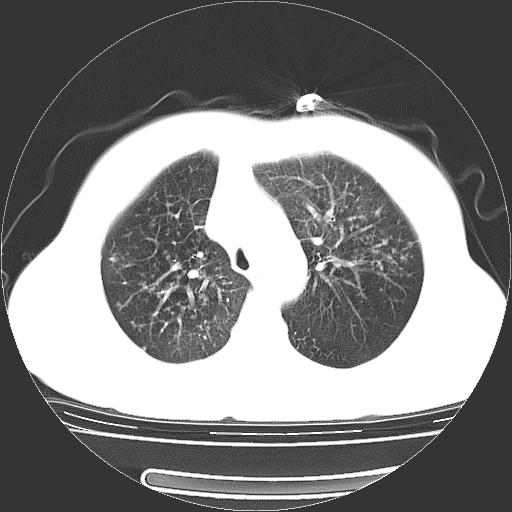

标题: CT23067:女,70岁,咳嗽、咳痰一个月,低热一周。 [打印本页]

女,70岁,咳嗽、咳痰一个月,低热一周。

1.左上肺结核,部分纤维化。右肺中下叶部分肺不张,内见液化、坏死及点状钙化,右中下叶支气管壁增厚、管腔狭窄,见多个点状钙化,结合临床考虑支气管内膜结核,建议痰检查抗酸杆菌并参考血沉。两肺多个小圆点状高密度灶,境界模糊,多考虑结核肺内播散。但本人年龄较大首先应支气管镜检以除外右肺癌。

2.胸主动脉夹层。